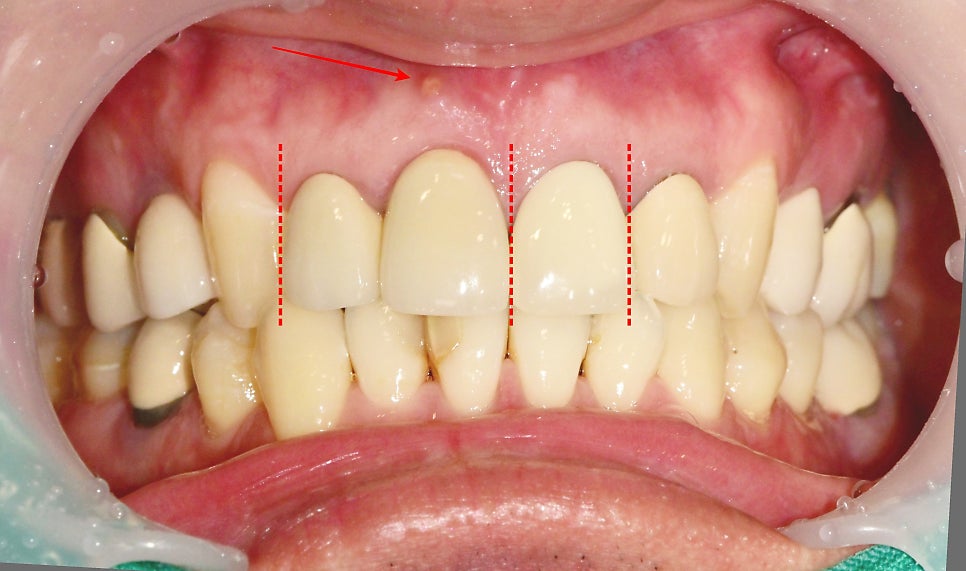

과거 앞니에 한 보철물 주변 잇몸이 불편감으로 내원해 주셨습니다.

치아 보철물은 각기 다른 시기에 제작되었고 1개 혹은 2개 치아가 한 덩어리의 보철물로 이루어져 있습니다.

먼저 화살표를 보시면 잇몸에 동그란 고름 주머니가 생겨있습니다.

과거에 한 보철물의 경계 부위가 시간이 지남에 따라

오염이 되면서 치아 뿌리 쪽에 염증이 생긴 걸로 판단이 됩니다.

최종 보철물의 형태와 색상

최종 앞니 심미보철 부착 후 사진입니다.

새로운 보철만 바꿨을 뿐인데

기존 치아들까지 부드러운 느낌을 주는 것 같습니다.

주변 치아의 색상을 고려하고

과거의 보철물은 잇몸과의 경계 부위가 자연스럽지 못하고

형태가 투박해 보였습니다.

그 점을 고려하여 치아의 형태를 자연스럽게 제작하려고 노력했습니다.

이번에 치료한 치아 옆의 과거의 보철물도 같이 교체를 했다면

훨씬 자연스러웠을 텐데

일단 큰 불편감 먼저 해소하고 나중에 고민하기로 했습니다.

문제가 생긴 2개의치아는 신경치료

나머지 1개의 치아는 보강 후신경치료 없이 앞니 보철치료를 마무리했습니다.